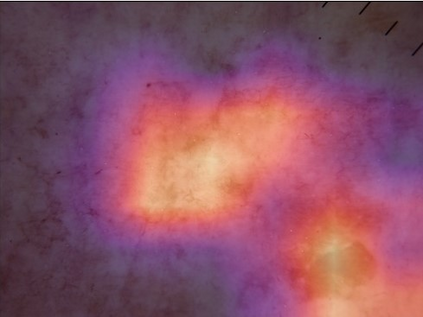

State-of-the-art deep learning approaches for skin lesion recognition often require pretraining on larger and more varied datasets, to overcome the generalization limitations derived from the reduced size of the skin lesion imaging datasets. ImageNet is often used as the pretraining dataset, but its transferring potential is hindered by the domain gap between the source dataset and the target dermatoscopic scenario. In this work, we introduce a novel pretraining approach that sequentially trains a series of Self-Supervised Learning pretext tasks and only requires the unlabeled skin lesion imaging data. We present a simple methodology to establish an ordering that defines a pretext task curriculum. For the multi-class skin lesion classification problem, and ISIC-2019 dataset, we provide experimental evidence showing that: i) a model pretrained by a curriculum of pretext tasks outperforms models pretrained by individual pretext tasks, and ii) a model pretrained by the optimal pretext task curriculum outperforms a model pretrained on ImageNet. We demonstrate that this performance gain is related to the fact that the curriculum of pretext tasks better focuses the attention of the final model on the skin lesion. Beyond performance improvement, this strategy allows for a large reduction in the training time with respect to ImageNet pretraining, which is especially advantageous for network architectures tailored for a specific problem.